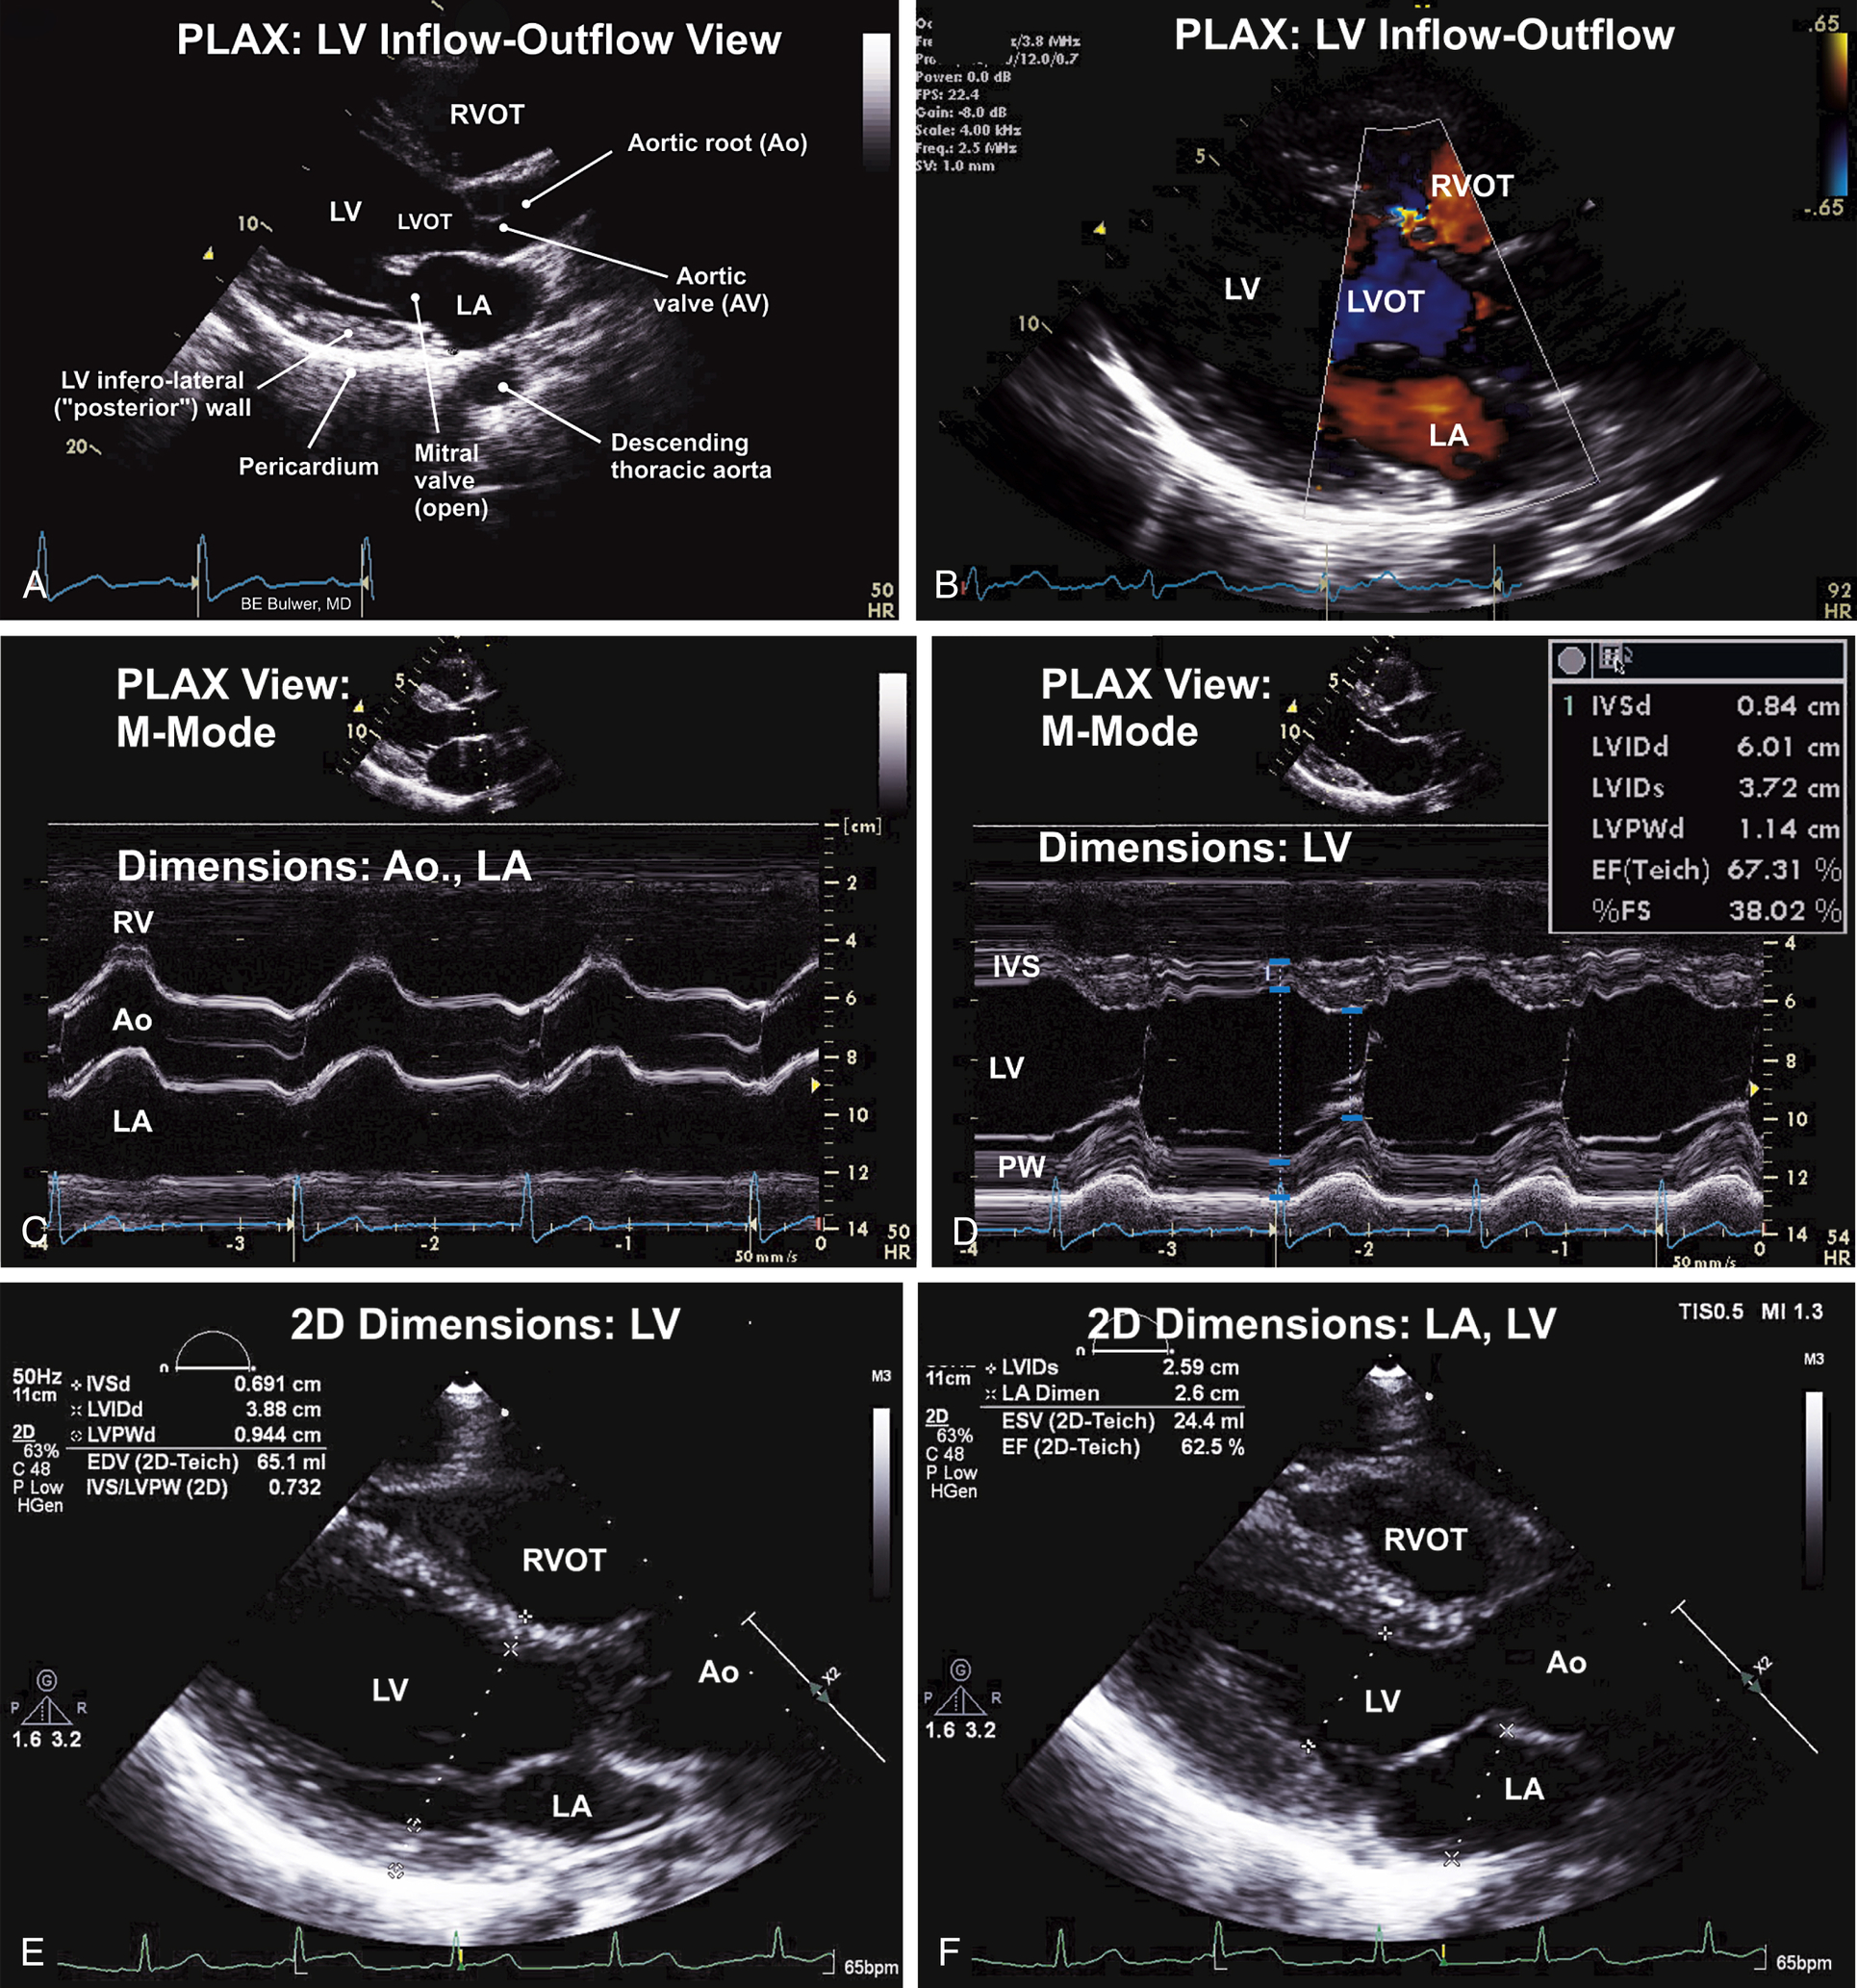

| Parasternal Views (see Figs. 9.1–9.4) | ||

| Parasternal (P) | Long-axis (LAX) | LV inflow-outflow, LA, MV, LV, LVOT, RVOT, IVS, Aortic root, descending thoracic aorta |

Parasternal Long-Axis Views: Normal Examination (see Figs. 9.1 and 9.2)